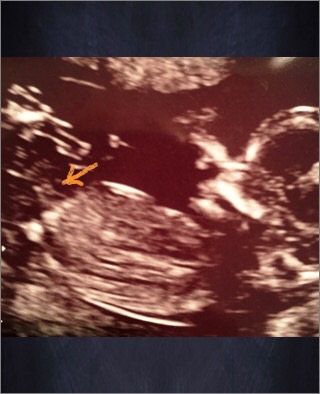

Does it look like the nub? :) Attachment 23516

I think so!!! Girl lean!

Boy guess

boy lean

Maybe boy?

Thinking boy

leaning boy